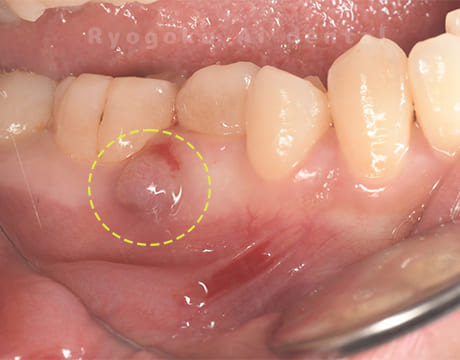

Case05

- 原因

- 慢性根尖性歯周炎

- 治療内容

- マイクロエンド

- 治療費用

- 121,000円(被せ物は含まない)

他院ではお薬の交換と抗生剤の処方で経過を診ていた患者さんです。歯茎の腫れが治らないとのことで、根管治療を開始し、2回目のご来院で腫れが引いたケースです。現在は被せ物も入り、良好に経過しております。